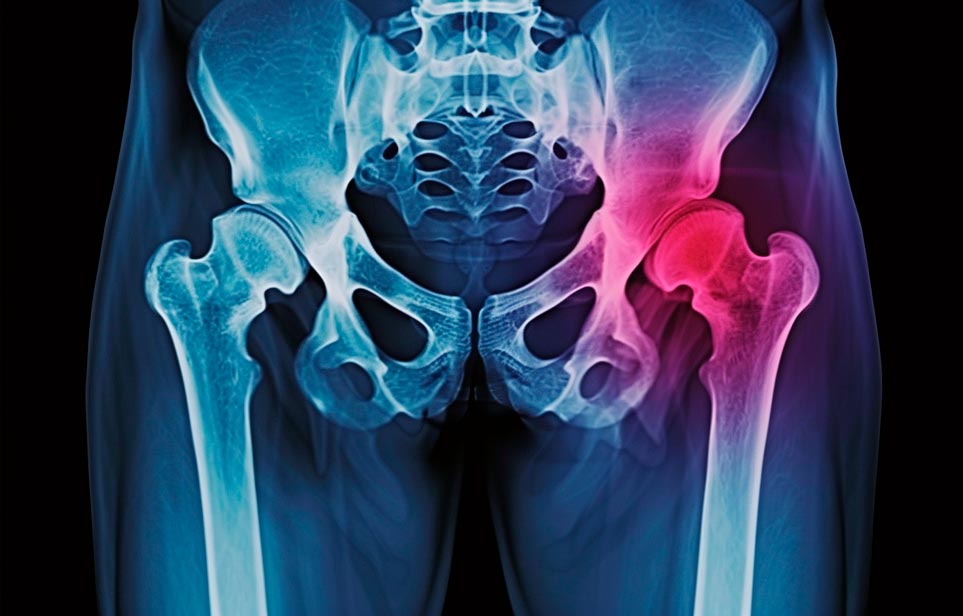

Реабилитация пожилых после перелома шейки бедра в Калининграде

Эффективная и профессиональная реабилитация после перелома шейки бедра в Калининграде осуществляется по демократичным ценам лучшими специалистами современной медицинской клиники «Заботливые люди» с применением персонального подхода к каждому пожилому человеку с такой тяжёлой травмой бедренной кости ноги. В процессе осуществления такой специализированной услуги все наши пациенты имеют возможность получения качественного и достойного обслуживания, эффективного восстановления. Лучший дом престарелых позаботиться о Вашем близком человеке.

Такая травма в большей части случаев возникает у граждан преклонного возраста. При её появлении на протяжении длительного времени сохраняются болевые и неприятные ощущения в области паха, при которых серьёзно ухудшается качество жизни, возникает множество последствий для его жизни и здоровья.

По какой симптоматике можно определить перелом шейки бедра

- Визуально повреждённая нога сокращается на несколько сантиметром из-за сокращения мышц.

- Стопа выворачивается наружу.

- В лежачем положении человек не может поднять ногу.

При такой симптоматике важно незамедлительно обращаться к специалистам для получения всей необходимой помощи, терапии и восстановления после перелома шейки бедра. Если не оказать помощи старику, то это приведёт к гноению, инвалидности, иным видам осложнений.